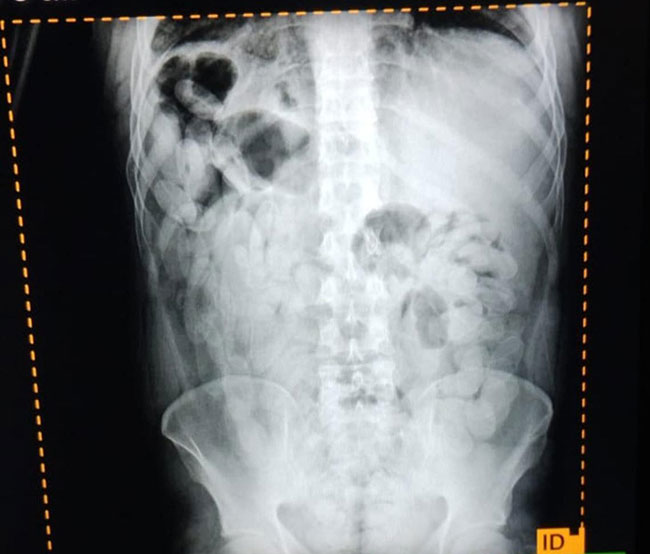

Ante las altas posibilidades de estar frente a la modalidad de traslado de estupefacientes denominada "capsulero" y para preservar la salud de las personas, se solicitó asistencia de emergencia y el traslado al Nosocomio local, en donde mediante placas radiográficas pudieron confirmar la presencia de cápsulas.

Luego, los involucrados evacuaron 180 cápsulas que sometidas a la prueba de campo narcotest dieron resultado positivo para cocaína con un peso total de 2 kilos 102 gramos.